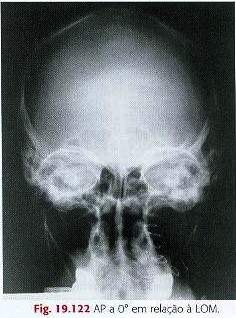

Incidência AP a 0° do Trauma:

Todo o crânio é visualizado na radiografia.

Cristas petrosas superpostas na região orbital superior.

Pirâmides petrosas preenchem as órbitas com os meatos acústicos

internos vistos horizontalmente através do centro das órbitas.

A distância da linha orbitária oblíqua até a margem lateral do

crânio é igual em ambos os lados.

Dorso selar e clinóides anteriores são visualizados superiormente

aos seios etmoidais.

Densidade e contraste suficientes estão presentes, sem

movimentação, para visualização clara do osso frontal.